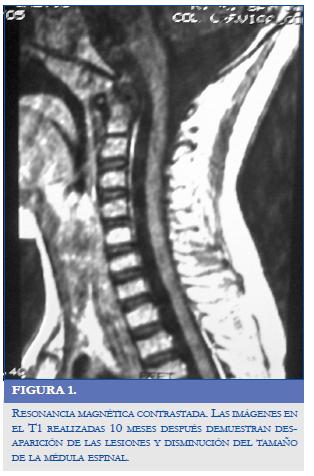

Las nuevas imágenes de RM del encéfalo y la médula espinal realizadas 10 meses después demostraron desaparición de las lesiones nodulares y disminución del volumen de la médula espinal cervical (Figura 2).

No es clara la indicación de la cirugía en el tratamiento de los histoplasmomas del SNC. La mayoría de los pacientes, como el niño descrito en este artículo, tienen múltiples lesiones, frecuentemente localizadas en áreas elocuentes del SNC que no pueden ser abordadas fácilmente. Además, con el tratamiento antifúngico la mayoría de las lesiones desaparecen, como lo manifestado en este caso (Figura 2). En conclusión, la cirugía es innecesaria y no se recomienda en la mayoría de los casos de lesiones focales del SNC (3). Sólo estaría indicada en los casos de déficit neurológico progresivo a pesar del tratamiento antifúngico o ante la incertidumbre diagnóstica (11).